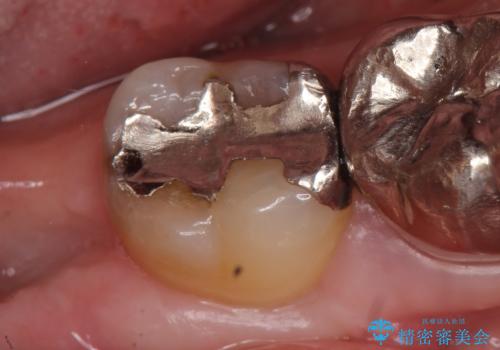

- 冷たいものを飲むと右下の奥歯が痛むので診て欲しいといらっしゃった方の症例です。

銀歯及び虫歯を除去後、より適合の良いPGA(ゴールド)インレーによる修復を行いました。